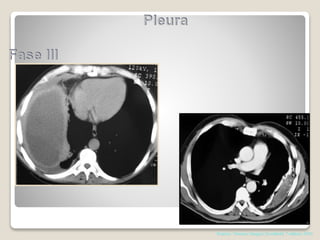

Fases

1-EXSUDATIVA NÃO COMPLICADO

2 FIBRINO-PURULENTA

3 ORGANIZAÇÃO

COMPLICADO

Shields. Thoracic Surgery,Clinics 7 edition; 2015

tratamento

•Antibióticos

•Toracocentese

•Drenagem Pleural

•Decorticação Pulmonar

•Pleurostomia (sem condições clínicas de decorticação)